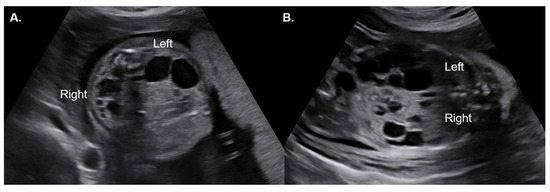

Prenatal Diagnosis and Postnatal Outcomes of Fetal ADPKD: A Single-Center Retrospective Cohort Study

Background/Objectives: Autosomal dominant polycystic kidney disease (ADPKD) is the most common hereditary renal disorder; it is typically diagnosed in adulthood, but occasionally presents antenatally as very-early onset ADPKD. Despite advances in prenatal ultrasonography, knowledge regarding the postnatal course of fetal ADPKD remains limited, [...] Read more.

Background/Objectives: Autosomal dominant polycystic kidney disease (ADPKD) is the most common hereditary renal disorder; it is typically diagnosed in adulthood, but occasionally presents antenatally as very-early onset ADPKD. Despite advances in prenatal ultrasonography, knowledge regarding the postnatal course of fetal ADPKD remains limited, restricting reliable prognostic assessment and prenatal counselling. This study aimed to evaluate the prenatal sonographic features of fetal ADPKD and their correlation with postnatal outcomes. Materials and Methods: We retrospectively reviewed 20 cases of prenatally suspected ADPKD diagnosed at a single tertiary referral center between 2006 and 2024. Prenatal ultrasonographic findings including renal size, cortical echogenicity, corticomedullary differentiation (CMD), and cortical cysts were analyzed and correlated with postnatal clinical and genetic outcomes. Postnatal follow-up data, including renal function and progression to chronic kidney disease (CKD), were collected with a median follow-up of 93.6 months. Results: The most consistent prenatal ultrasonographic findings were increased cortical echogenicity (85%), increased CMD (75%), and renal enlargement (35%), with cortical cysts detected in 45% of cases. Amniotic fluid volume was preserved in most cases (80%). Postnatally, most infants maintained normal or near-normal renal function, although two progressed to CKD. Both CKD cases demonstrated absent CMD on prenatal imaging. Sonographic features resembling autosomal recessive polycystic kidney disease (ARPKD) were associated with adverse outcomes. Although CMD severity showed no correlation with short-term neonatal outcomes, loss of CMD may still serve as a potential early indicator of long-term renal dysfunction. Conclusions: Fetal ADPKD was associated with heterogeneous postnatal outcomes. Loss of CMD and ARPKD-like sonographic appearances may be associated with adverse prognosis, whereas most infants maintained preserved renal function. Early recognition of ADPKD is crucial for accurate counselling, appropriate perinatal management, and long-term surveillance. Full article